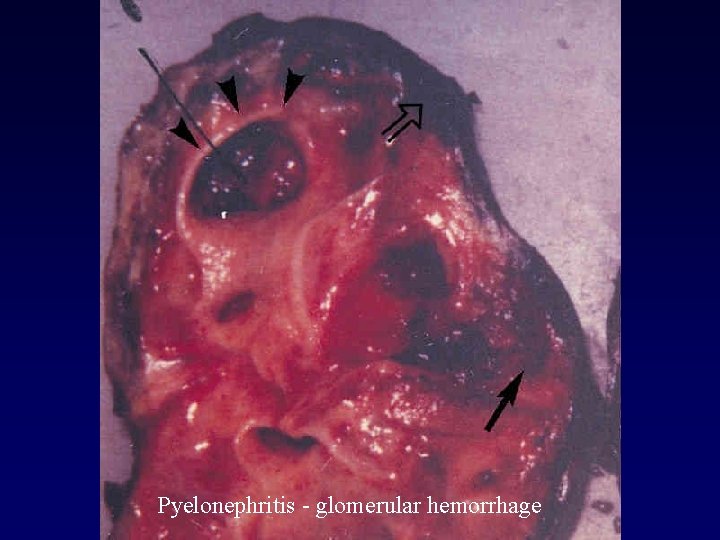

Pyelonephritis - glomerular hemorrhage